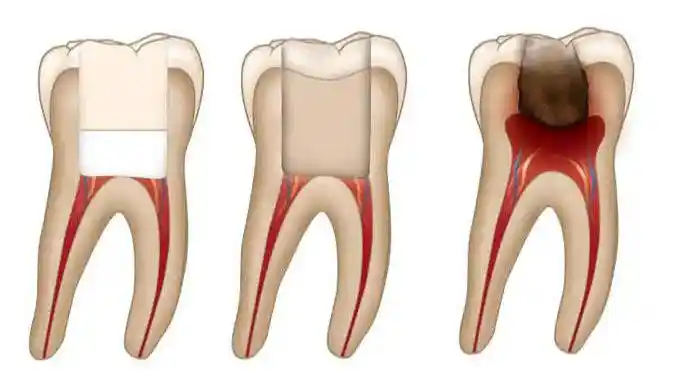

Caries Profundas

Cuando una caries ha penetrado profundamente hasta la pulpa, pero el daño no es extenso, una pulpotomía puede ser la solución adecuada para eliminar la parte afectada y mantener el resto del diente viable.

Remoción de la Pulpa Afectada

Se accede a la cámara pulpar, y se retira la pulpa afectada cuidadosamente, asegurándose de preservar el tejido sano. Esto es crítico para el éxito del tratamiento.

Aplicación de Agentes Terapéuticos

Una vez que la pulpa dañada ha sido removida, se aplican agentes terapéuticos como el hidróxido de calcio o el MTA, que ayudan a proteger el tejido pulpar restante y promueven la cicatrización.